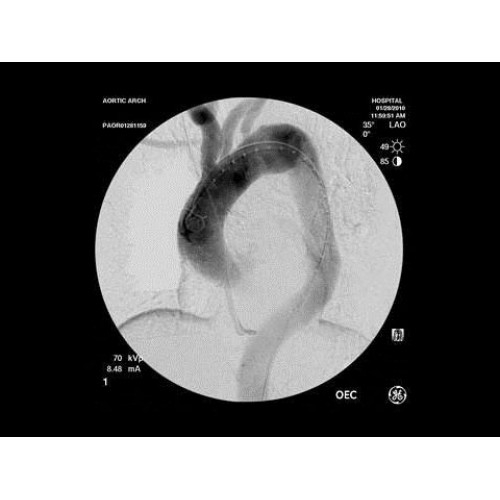

Рентген аппарат GE OEC 9900 Elite

Инновационная мобильная С-дуговая система для интраоперационной визуализации с высоким разрешением. Обеспечивает хирургов качественным изображением в реальном времени при минимальной лучевой нагрузке. Усовершенствованная эргономика позволяет легко позиционировать аппарат в условиях операционной. Поддерживает интеграцию с современными хирургическими навигационными системами.

Передовая рентгенохирургическая система GE OEC 9900 Elite представляет собой инновационное решение для проведения широкого спектра малоинвазивных вмешательств. Это оборудование премиум-класса сочетает высочайшее качество визуализации с интуитивно понятным управлением, устанавливая новые стандарты в области интраоперационной рентгеноскопии.

GE OEC 9900 Elite оснащен революционной системой визуализации, обеспечивающей кристально четкое изображение анатомических структур. Интеллектуальная система автоматически адаптирует параметры исследования под конкретную хирургическую задачу, обеспечивая оптимальный баланс между качеством изображения и лучевой нагрузкой. Особое внимание уделено удобству работы операционной бригады.

• Кардиохирургические вмешательства и ангиопластика

• Эндоваскулярная нейрохирургия

• Ортопедические и травматологические операции

• Урологические и гинекологические вмешательства

• Чрескожные дренирования и биопсии

• Сосудистая хирургия

В ведущих медицинских центрах GE OEC 9900 Elite успешно применяется для проведения сложных кардиологических, нейрохирургических и ортопедических вмешательств. Система доказала свою эффективность при выполнении стентирования коронарных артерий, эмболизации сосудов головного мозга и вертебропластики. Многие учреждения отмечают повышение качества операций после внедрения этого оборудования.